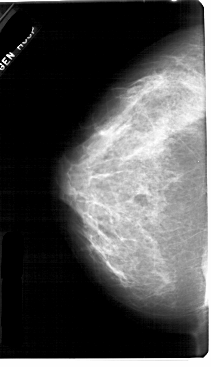

A_1752_1.RIGHT_MLO

LEFT_CC LINES 5491 PIXELS_PER_LINE 3151 BITS_PER_PIXEL 12 RESOLUTION 43.5 NON_OVERLAY